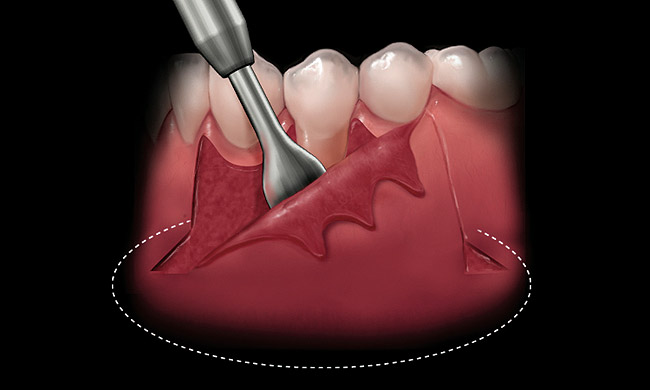

Coronal to the Burrow’s triangles using a new 15C blade, an incision should be carried across the apical extent of the split thickness bed down to the underlying bone (Figure 4). Using a periosteal elevator, a full thickness flap should be reflected from the horizontal incision to a level approximately 5 mm to 10 mm apical to the Burrow’s triangles (Figure 5). Undermining of the tissue bilaterally will aid in flap placement and closure.

Figure 4  At the mucogingival junction, an incision is made to the underlying bone.

Figure 4

Figure 5  A periosteal elevator is used to create a full thickness elevation apical to the mucogingival junction.

Figure 5